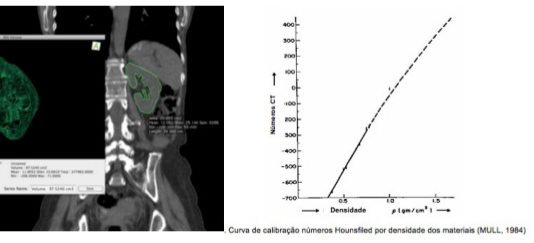

PET/CT: Fatores que afetam o SUV

Existem muitos fatores que podem alterar o valor padronizado de captação (SUV) nas imagens PET/CT. Um fluxo adequado e procedimentos...